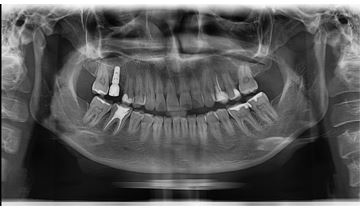

Өвдөлтгүй түргэн хугацаанд шинэ технологиор мэс ажилбарыг хийж байна. Имплант нь шүд байхгүй хэсэгт эрүүний ясанд унасан шүдний ёзоорын үүргийг гүйцэтгэдэг тусгай титанаар хийсэн эргийг суулган, эрүүний ястай бүрэн бэхжсэний дараа хиймэл цөгцийг холбон, өөрийн шүд шиг ашиглаж болох хиймэл шүдийг хэлнэ. Имплантын давуу тал нь энгийн хиймэл авагддаггүй, өөрийн шүдний 90% тай тэнцэх шүд учраас маш эвтэйхэн зовиургүй байдаг.

2020 онд манай ОРГИЛДЕНТ шүдний эмнэлгийн эмч нарын баг шүд шилжүүлэн суулгах мэс ажилбарыг 11 хүнд амжилттай хийлээ . Таны араа шүд хэрвээ эмчилгээ авахгүй , авахуулах шаардлагатай байгаа бол шүдээ авахуулсны дараа хиймэл шүд хийлгэлгүйгээр өөрийн агт араа шүдийг ашиглан зажлах үйлээ хадгалан үлдэх боломжтой боллоо .